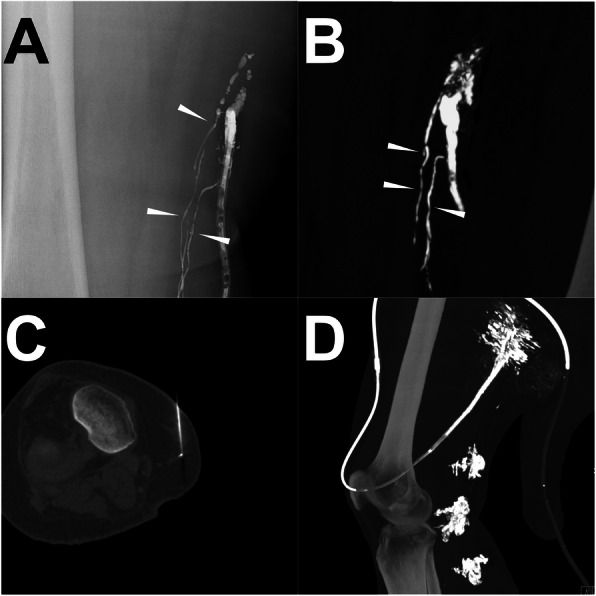

Fig. 1.

Illustration of the iodized oil-based LAG and post-LAG CT performance. Note: A patient with occurring persistent postoperative LF in the right groin after endovascular artery repair for an infrarenal abdominal aneurysm through the right femoral artery route. In the iodized oil-based LAG procedure, a total of 15 ml of lipiodol was injected with a velocity of 1 ml/min. However, due to the slow outflow of the lipiodol, 20 min after the accomplishment of the injection, the lipiodol only went up to the middle third of the thigh (black arrowhead) under the fluoroscopy and no obvious extravasation was found (a). 4 h later, the post-LAG CT was sequentially performed. The coronal (b) and sagittal (c) MIP images show definite extravasation of lipiodol (white arrowhead) at the right thigh with at least two points. The 3D-VR image (d) clearly visualized the major flowing route of the lymphatic fluid from calf to groin (white arrow) and the LF points (white arrowhead). Besides, abnormal lymphatic collateralization in calf could be observed (d). Abbreviations: LF – lymphatic fistula; LAG – lymphangiography; post-LAG CT – post-lymphangiographic computed tomography; MIP – maximum intensity projection; 3D-VR – three-dimensional volume rendering; LVs – lymphatic vessels